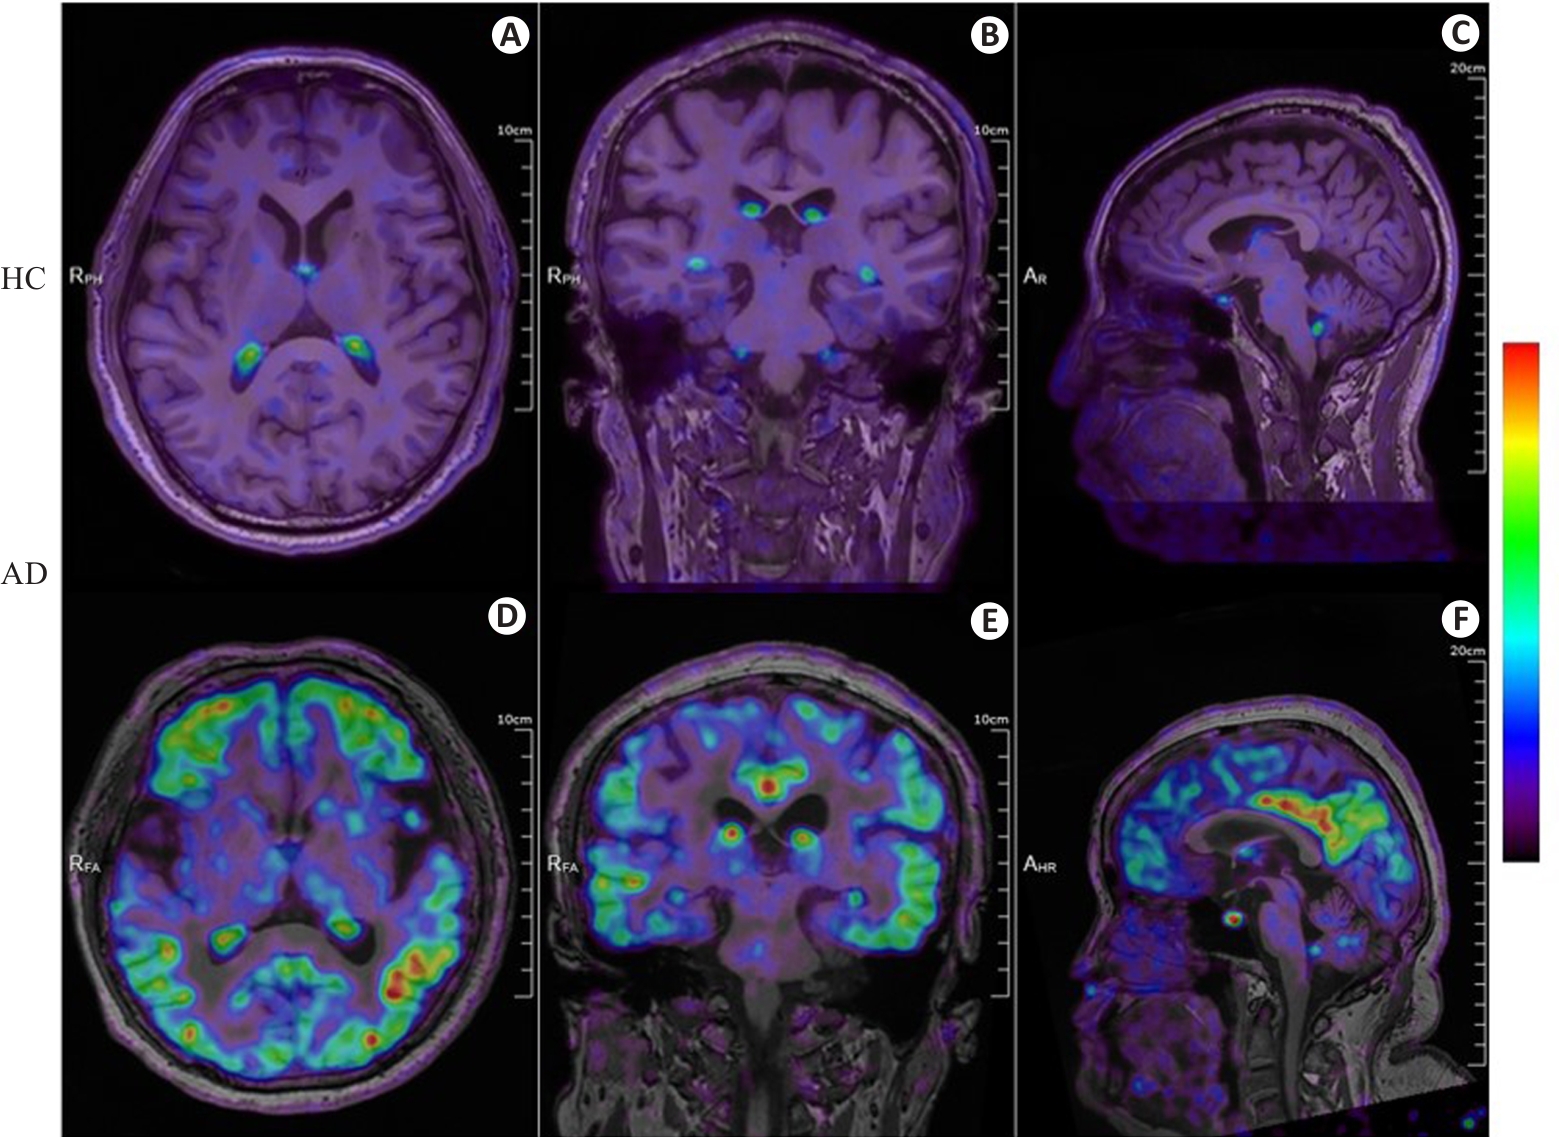

Fig.2 18F-APN-1607 PET/MR fusion imaging of a healthy control individual and an AD patient. A-C: Axial, coronal, and sagittal PET/MR fusion images of the brain of a male healthy control individual (72 years old, education years: 12; MMSE: 28, MoCa: 29; CDR: 0), showing physiological uptake in the choroid plexus without significant deposition of Tau protein in the remaining cerebrum and cerebellum. D-F: Axial, coronal, and sagittal PET/MR fusion images of the brain of a female AD patient (58 years old, education years: 12; MMSE: 5; MoCa: 2; CDR: 2) with diffuse and heterogeneous Tau protein deposition in the bilateral frontal, parietal, temporal, and occipital cortical regions. The color bar in the figure represents SUV.